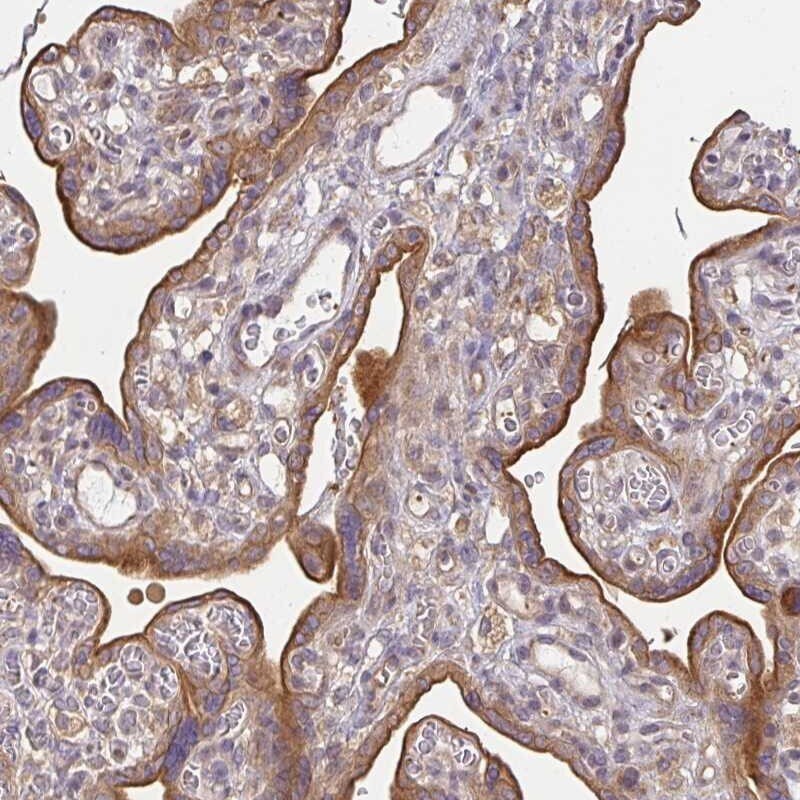

Supportive validation

- Submitted by

- Invitrogen Antibodies (provider)

- Main image

- Experimental details

- Immunohistochemical analysis of N6AMT2 in human placenta using N6AMT2 Polyclonal Antibody (Product # PA5-59169) shows moderate cytoplasmic and membranous positivity in trophoblastic cells.